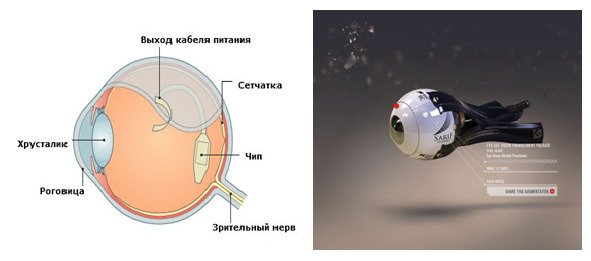

Офтальмологический имплантат

Офтальмологический имплантат

Имплантат сетчатки является имплантатом биомедицинской технологии, которые в настоящее время разрабатывается рядом частных компаний и научно-исследовательских институтов по всему миру. Имплантат предназначен для частичного восстановления полезного зрения людям, потерявшим зрение из-за дегенеративных заболеваний глаз, таких как пигментный ретинит или макулярная дегенерация.